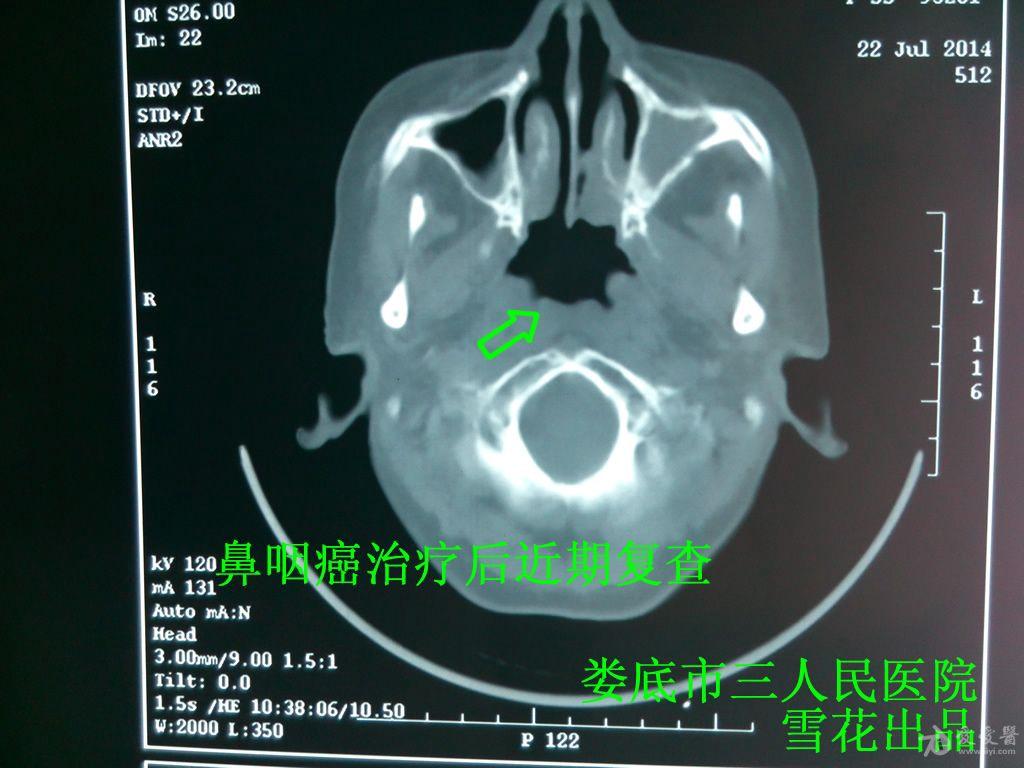

雪花医案第22期--没有颈淋巴结转移的鼻咽癌一定要化疗吗?

图片尺寸1024x768